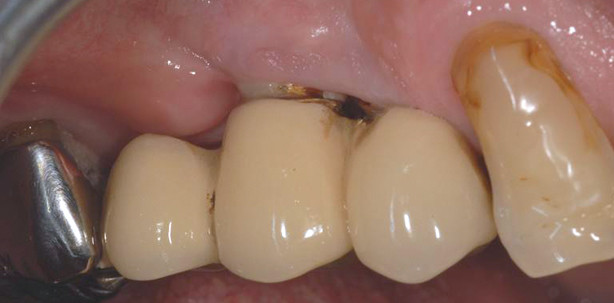

Im Rahmen der ausführlichen Untersuchung und Befundung im März 2012 wurden zudem an den Implantaten Regio 14 und 15 (Abb. 1) erhöhte Sondierungstiefen von 6 mm bzw. 7 mm, jeweils mit Blutung auf Sondierung (Abb. 2) festgestellt. Aufgrund der klinischen Hinweise auf eine Periimplantitis wurde eine röntgenologische Kontrolle der Implantate durchgeführt. Der Röntgenbefund (Abb. 3) ergab einen generalisierten horizontalen Knochenverlust Regio 14, 15 mit vertikalen Knocheneinbrüchen Regio 15 und bestätigte die Diagnose der Periimplantitis an beiden Implantaten. Als erste Therapiemaßnahme erfolgte im Rahmen der systematischen Parodontitistherapie das subgingivale Débridement auch an den Implantaten. Da sich bei der Reevaluation eine Persistenz der Blutung sowie der Taschentiefen ergab, wurde dem Patienten die unterstützende Applikation eines lokalen Antibiotikums an den Implantaten (ST ≥ 5 mm, Blutung auf Sondierung) vorgeschlagen – auch im Hinblick darauf, dass der Patient eine chirurgische Intervention zunächst einmal ablehnte, sodass die adjuvante Antibiose die einzige sinnvolle Therapieoption darstellte. An dieser Stelle sei darauf hingewiesen, dass bis dato keines der momentan in Deutschland auf dem Markt erhältlichen lokalen Antibiotika für die Behandlung periimplantärer Erkrankungen zugelassen ist.